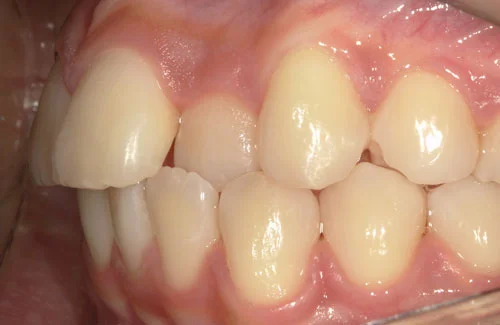

治療前後の写真

<症例3>前歯のクロスバイトでお悩み

右上の前歯2本が反対に咬合している、いわゆるクロスバイトが主訴でご来院なさいました。

主訴以外の部分には大きな叢生はなく、また患者様も装着時間をしっかり守ってくださったので約6ヶ月で改善することができました。

患者様と症状

主訴:上の前歯が出ている

性別・年齢:20代女性

問題点:上顎左側側切歯のクロスバイト、叢生

診断:前歯部の叢生を伴うアングルⅠ級の不正咬合

主なリスク:矯正中一時的に咬合しにくくなる、歯肉退縮

症状:叢生(そうせい) 上顎前突(じょうがくぜんとつ)

治療内容

治療期間:6ヶ月

治療費用:495,000円(税込)

プラン:14枚コース/ライトプラン

抜歯:親知らずのみ抜歯

再診治療費:無し

追加治療費:無し

保定装置費:無し

・2本の前歯が前突しておりましたが、矯正で自然な歯並びになりました。

・前歯の1本が下の歯の裏側に噛み合うクロスバイトになっていましたが、矯正で改善されました。